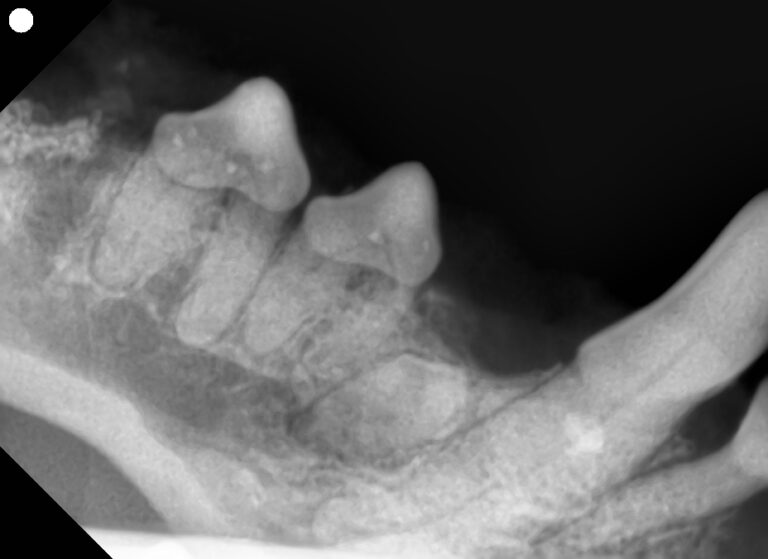

下の写真を見てみましょう。

左下顎の第四前臼歯から第三後臼歯にかけて、歯根や歯根の分岐部が見えています。

歯科レントゲンを撮影してみるとやはり歯槽骨の融解が進んでいました。

この歯はアタッチメントロスが50%以上、多根歯でステージⅢの根分岐病変を認めたため重度歯周病として抜歯が適応となります。